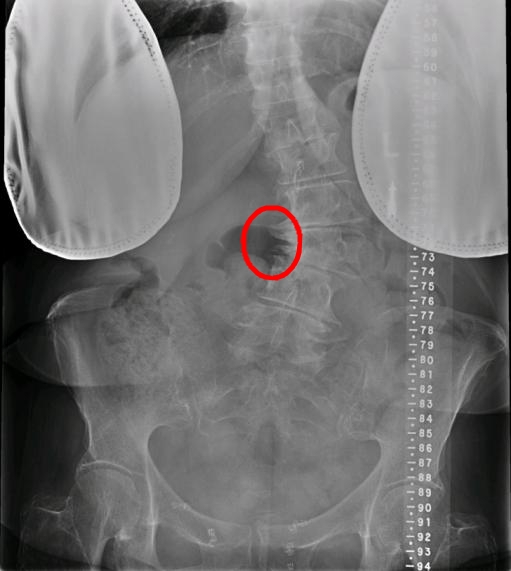

MRI可见局部弯曲凹侧神经根明显受压,腰椎X线可见椎体存在侧方滑移伴凹侧骨质增生硬化。

术前MRI示L4/5左侧神经根管狭窄